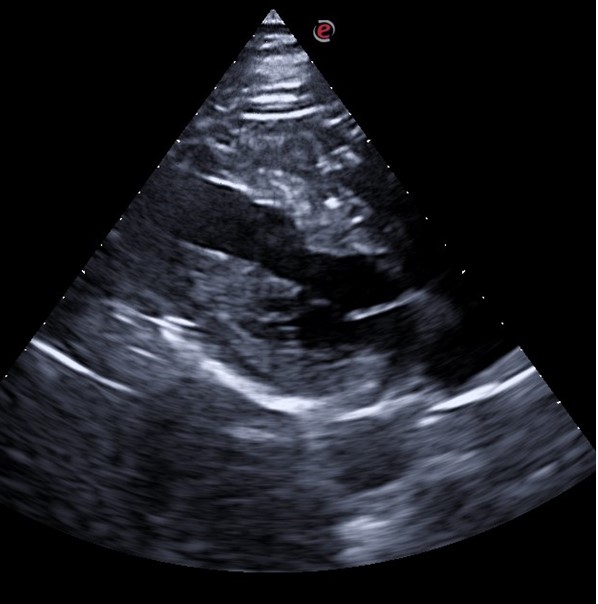

En nuestro centro se le realizó Ecocardioscopia: En eje paraesternal largo se observa grosor parietal aumentado más a nivel septal y de predominio en septo basal donde alcanza los 18 mm. VI no dilatado. FEVI conservada. No alteración de la contractilidad ni valvulopatías.